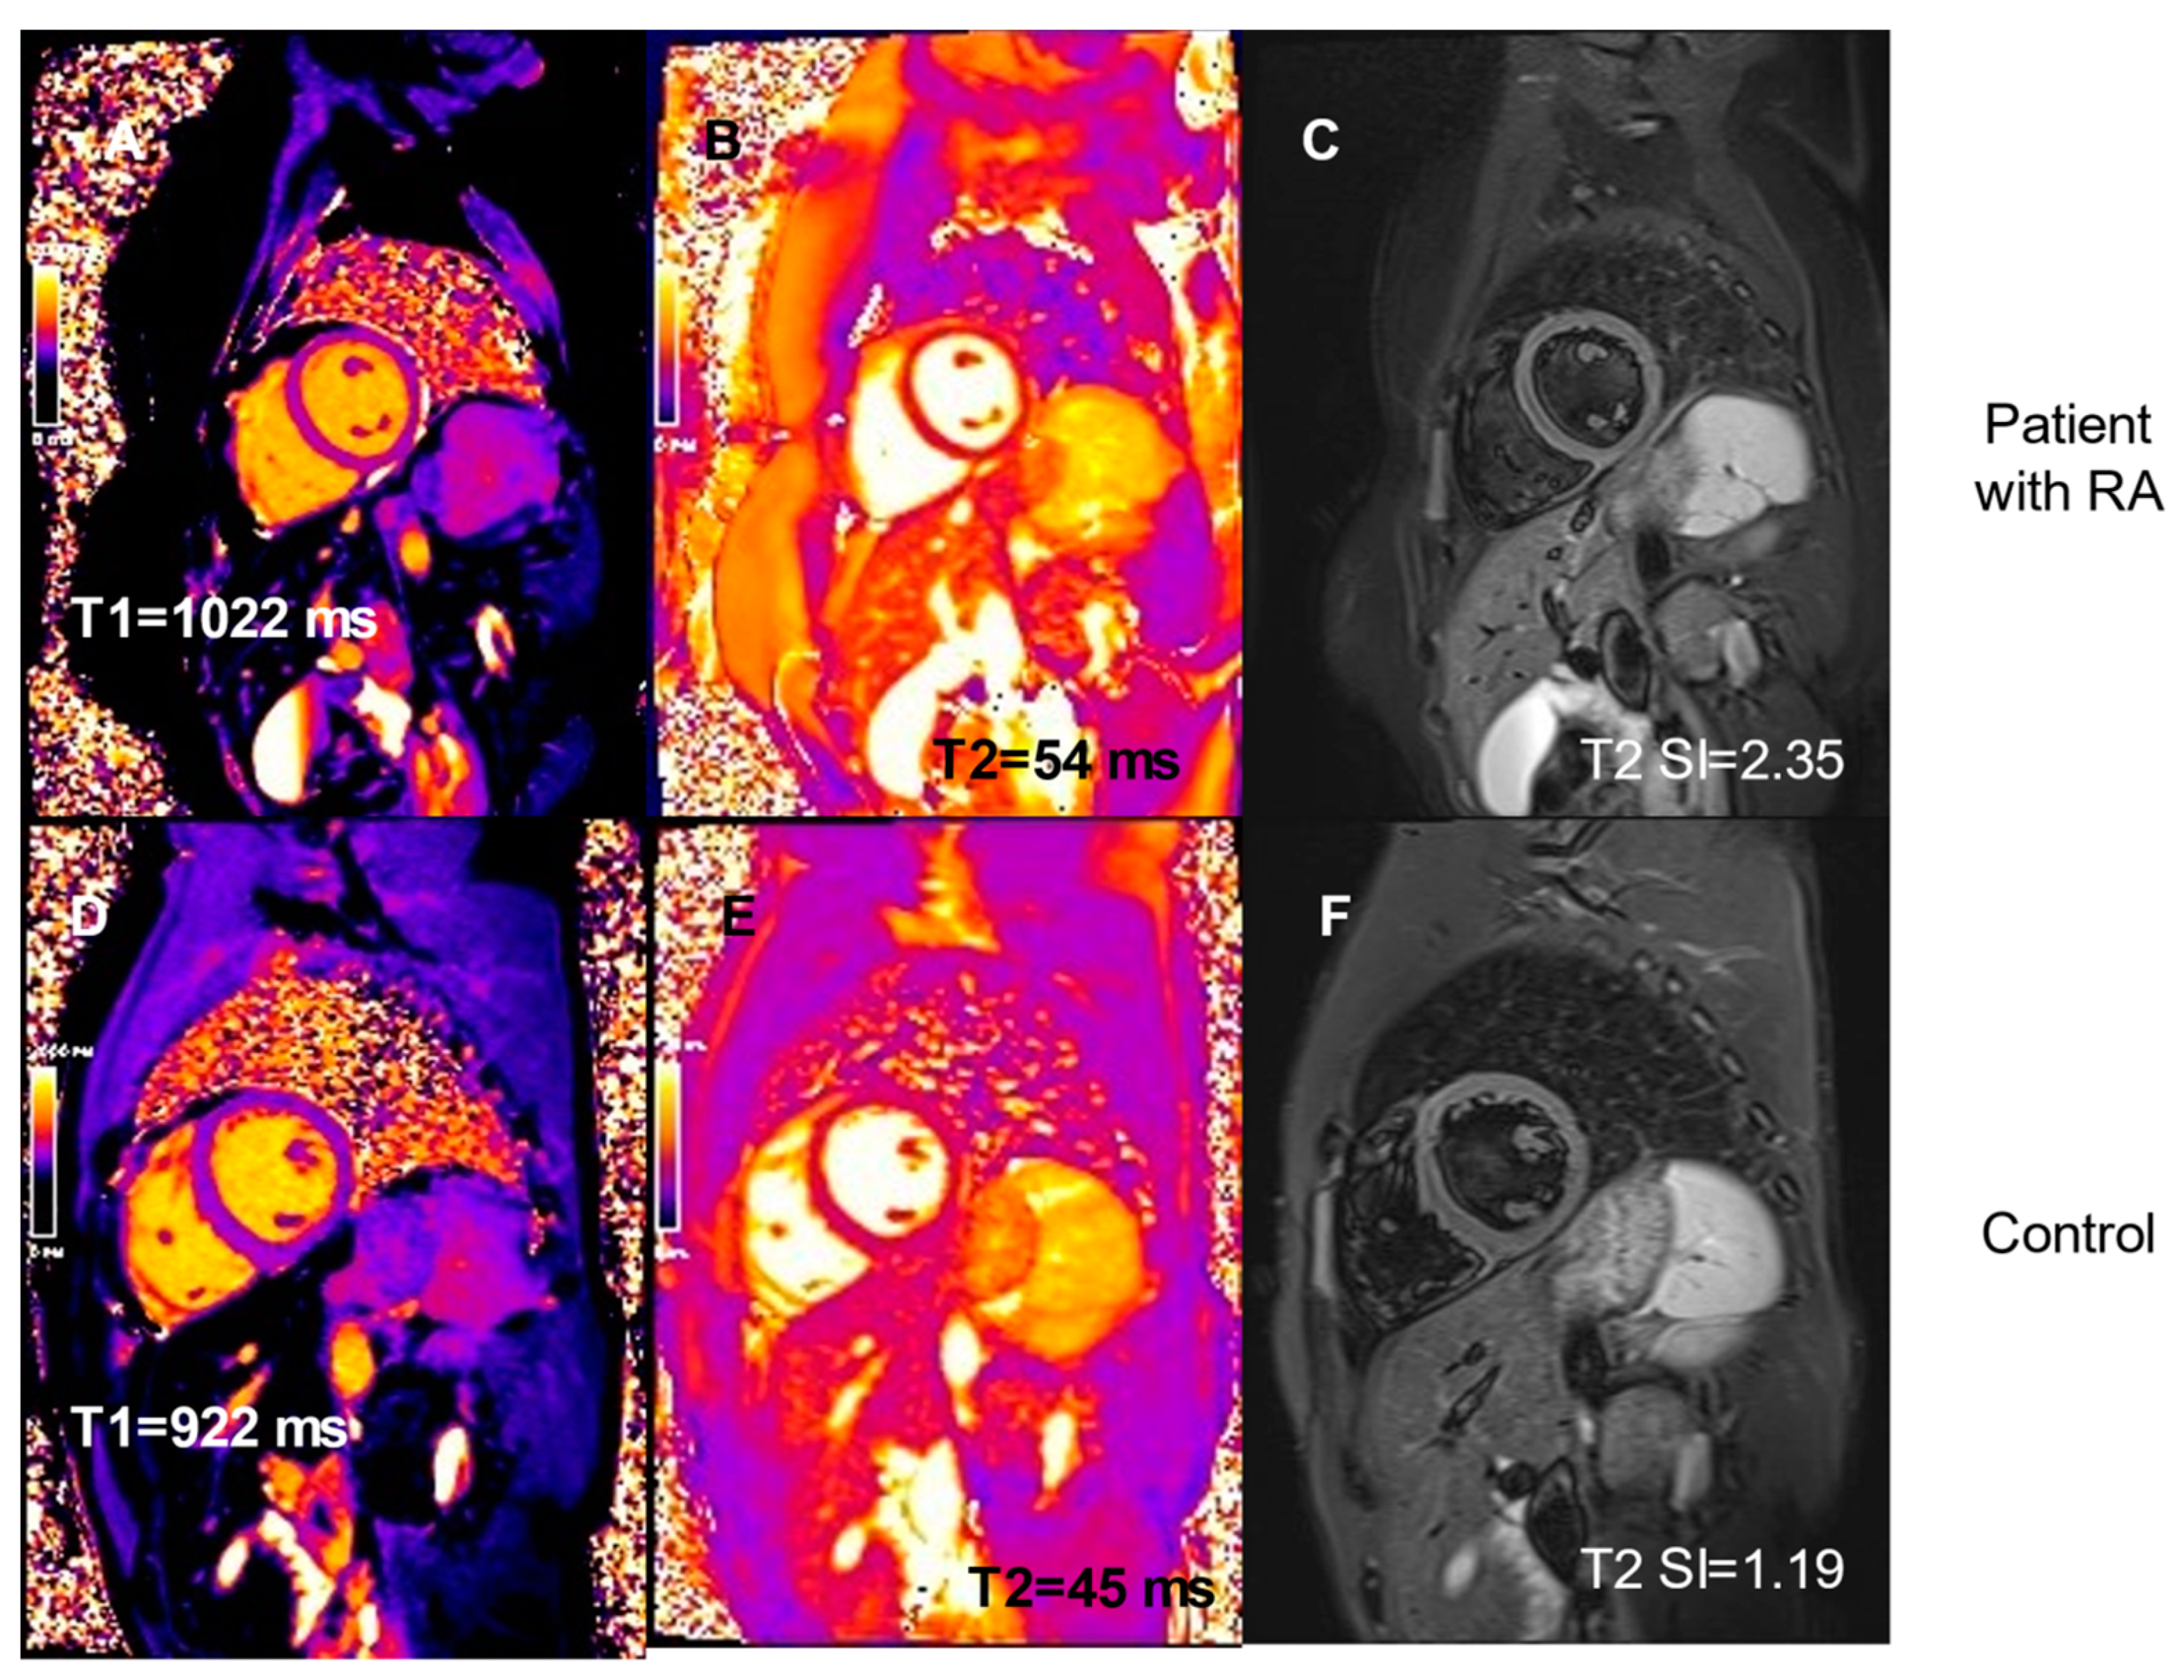

| T1 pre-contrast, median | 1028 (1001–1040) | 992 (984–1012) | 0.04 |

| (IQR), ms | |||

| T1post-contrast, median (IQR), ms | 507 (475–550) | 586 (565–593) | 0.0002 |

| T2, median (IQR), ms | 49 (48–50) | 45 (45–46) | 0.003 |

| T2 SI, median (IQR) | 1.92 (1.80–2.13) | 1.82 (1.47–1.88) | 0.06 |